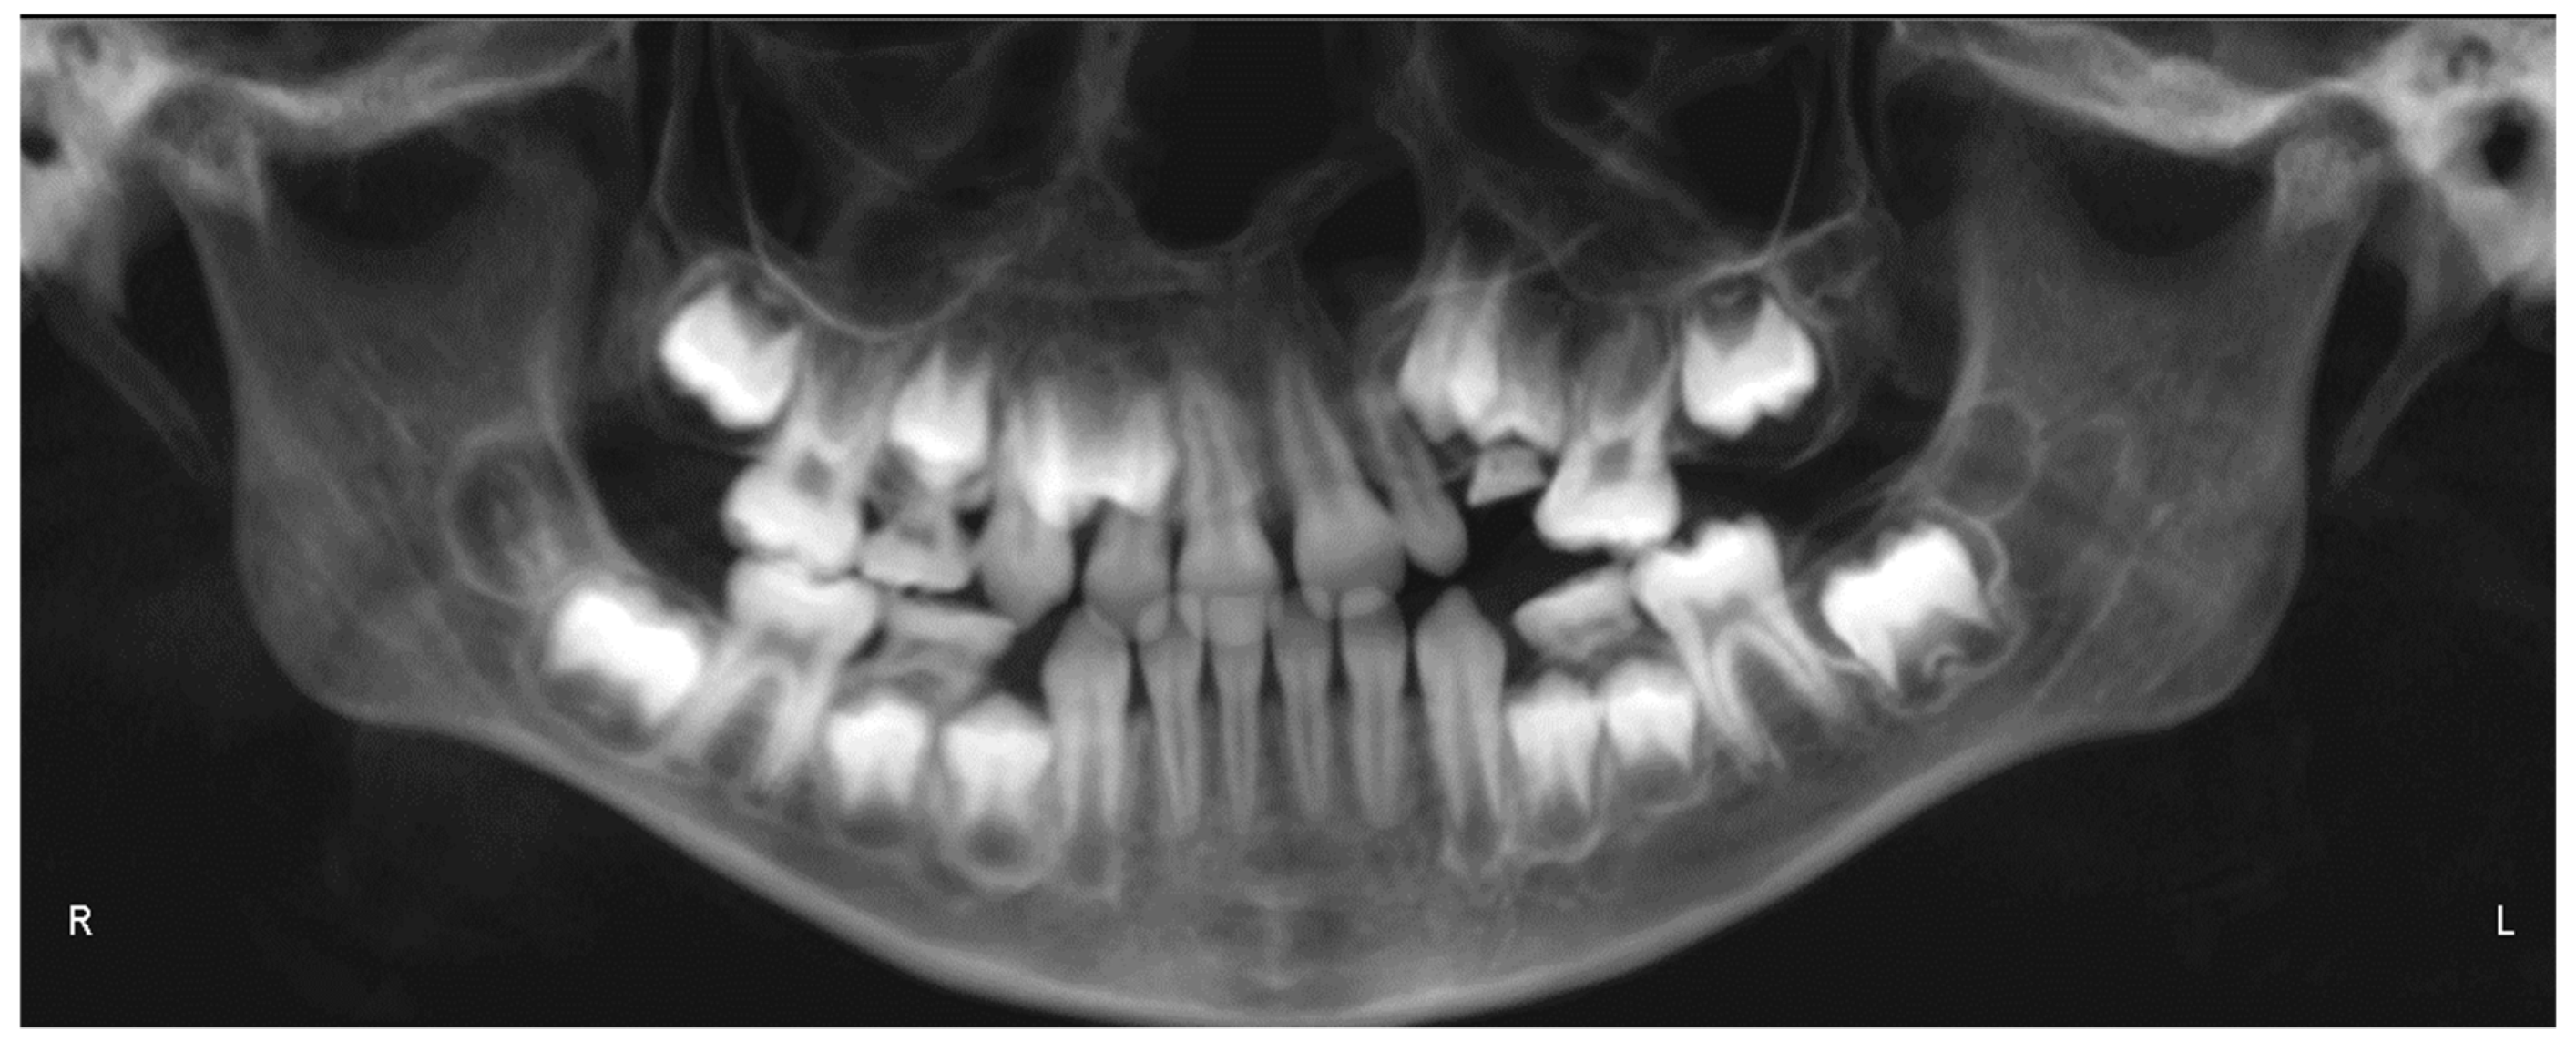

- Evaluation of impacted teeth, a common indication of CBCT in orthodontics. The advantages of CBCT include assessment of the tooth location and position, the stage of development, and status of adjacent teeth. CBCT is justified in these cases, because CBCT has the capability of evaluating the impacted teeth and adjacent structures more accurately than 2D conventional imaging. The benefit–risk ratio is favorable, especially if the CBCT volume is collimated to the impacted tooth. Figure 1, Figure 2, Figure 3 and Figure 4 show an example of impacted maxillary canines, and their proximity to the maxillary lateral incisors. Figure 1 shows an intraoral photograph. The benefit of CBCT acquisition in this case includes the ability to visualize the canines and the lateral incisors in three dimensions, which can be visualized in Figure 2 and Figure 3. In this case, the maxillary right lateral incisor exhibited external root resorption, a finding that would be difficult to see on a conventional 2D panoramic radiograph. Figure 4 shows a Maximum Intensity Projection of a panoramic view derived from the CBCT volume. This unique view is free of magnification, distortion, ghost images, and overlaps frequently seen in conventional 2D panoramic radiography.